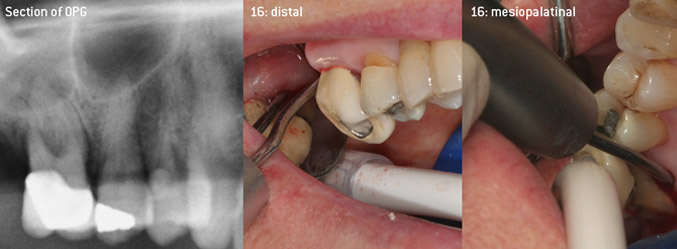

En tant qu'initiateurs du développement du nouvel insert détartreur à air N° 3AP avec un revêtement diamant, les deux dentistes ont reconnu la nécessité d'améliorer les restrictions de manipulation des inserts avec un revêtement diamant disponibles dans le commerce, en particulier lors du traitement des furcations et du travail dans des poches intra-osseuses étroites. Cela devrait être possible pour les procédures non-chirurgicales (figure 2) et chirurgicales (figure 3).

(Photos (Figures 2-4): © Dr. Christian Graetz)

L'objectif était de développer un insert universellement applicable afin d'éviter les changements d'insert qui prennent du temps. En outre, il devrait être plus facile d'utiliser les nouveaux inserts dans les poches intra-osseuses étroites à partir de l'entrée distale et à l'entrée distale de la furcation des molaires maxillaires, ce qui permettrait une utilisation plus efficace des instruments. Pour ce faire, une courbe d'instrument de plus grand diamètre a été utilisée (figure 1), ce qui est très avantageux pour le débridement fermé des dents présentant une perte d'attache avancée et une implication de la furcation en particulier (figure 4).